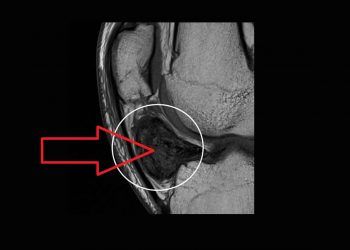

Villonodüler Sinovitis, sinovyal doku üremesi dev hücre ve mononükleer hücre infiltrasyonuyla belirgin bir şekilde oluşan sinovya zarının yangısına denir. Çoğunlukla...